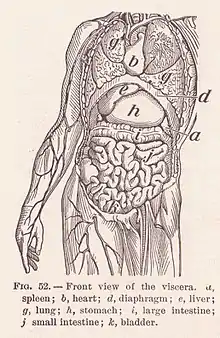

- Visceral and viscus (from Latin viscera 'internal organs'): associated with organs within the body's cavities.[57] For example, the stomach is covered with a lining called the visceral peritoneum as opposed to the parietal peritoneum. Viscus can also be used to mean "organ".[57] For example, the stomach is a viscus within the abdominal cavity, and visceral pain refers to pain originating from internal organs.